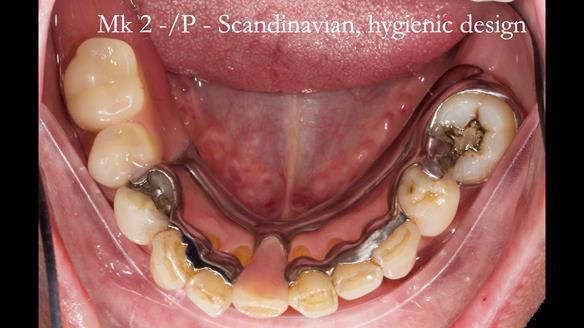

Welcome to my Newsletter 54 showing the making and fitting of dentures (a complete upper metal reinforced denture, a lower immediate partial denture and a definitive Scandinavian designed, metal based lower partial denture) for David, a 75 -year-old man. The full protocol workflow is presented including the use of dentate photographs to mimic his natural teeth.

Interestingly we found that the upper complete denture when finished and fitted didn’t have good enough retention for David’s satisfaction. It was relined by adding compound to the buccal flanges – to almost overextend into the sulcus to ‘create’ a sulcus, followed by using a light bodied silicone impression material. This improved the function of the C/-considerably. A lower Scandinavian hygienically designed lower RPD was also provided which helped with occlusal stability and reseating the upper denture – further improving the fit.